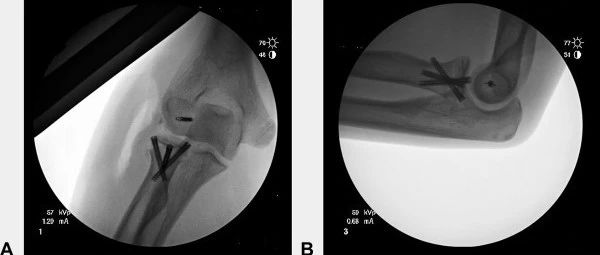

手把手教你:桡骨颈骨折,三脚架螺钉固定技术!

本文未经授权禁止转载桡骨头、桡骨颈骨折是最常见的肘部骨折之一,占所有骨折的2% - 5%,占肘部骨折的30%。虽然不复杂的Mason I型骨折可以非手术治疗,但Mason II-IV型骨折往往需要采用切开复位内固定进行治疗。其中,Mason II-III型骨折3个及以下骨折碎片通常采用切开复位和2 - 3颗拉力螺钉内固定治疗。对于横行、轴向不稳定的桡骨颈骨折,常常需要在螺钉固定基础上加用微型T型钢板或者锁定桡骨近端骨折钢板。最近,也有学者提出了微创的交叉螺钉或者是三脚架螺钉技术治疗桡骨颈骨折。...